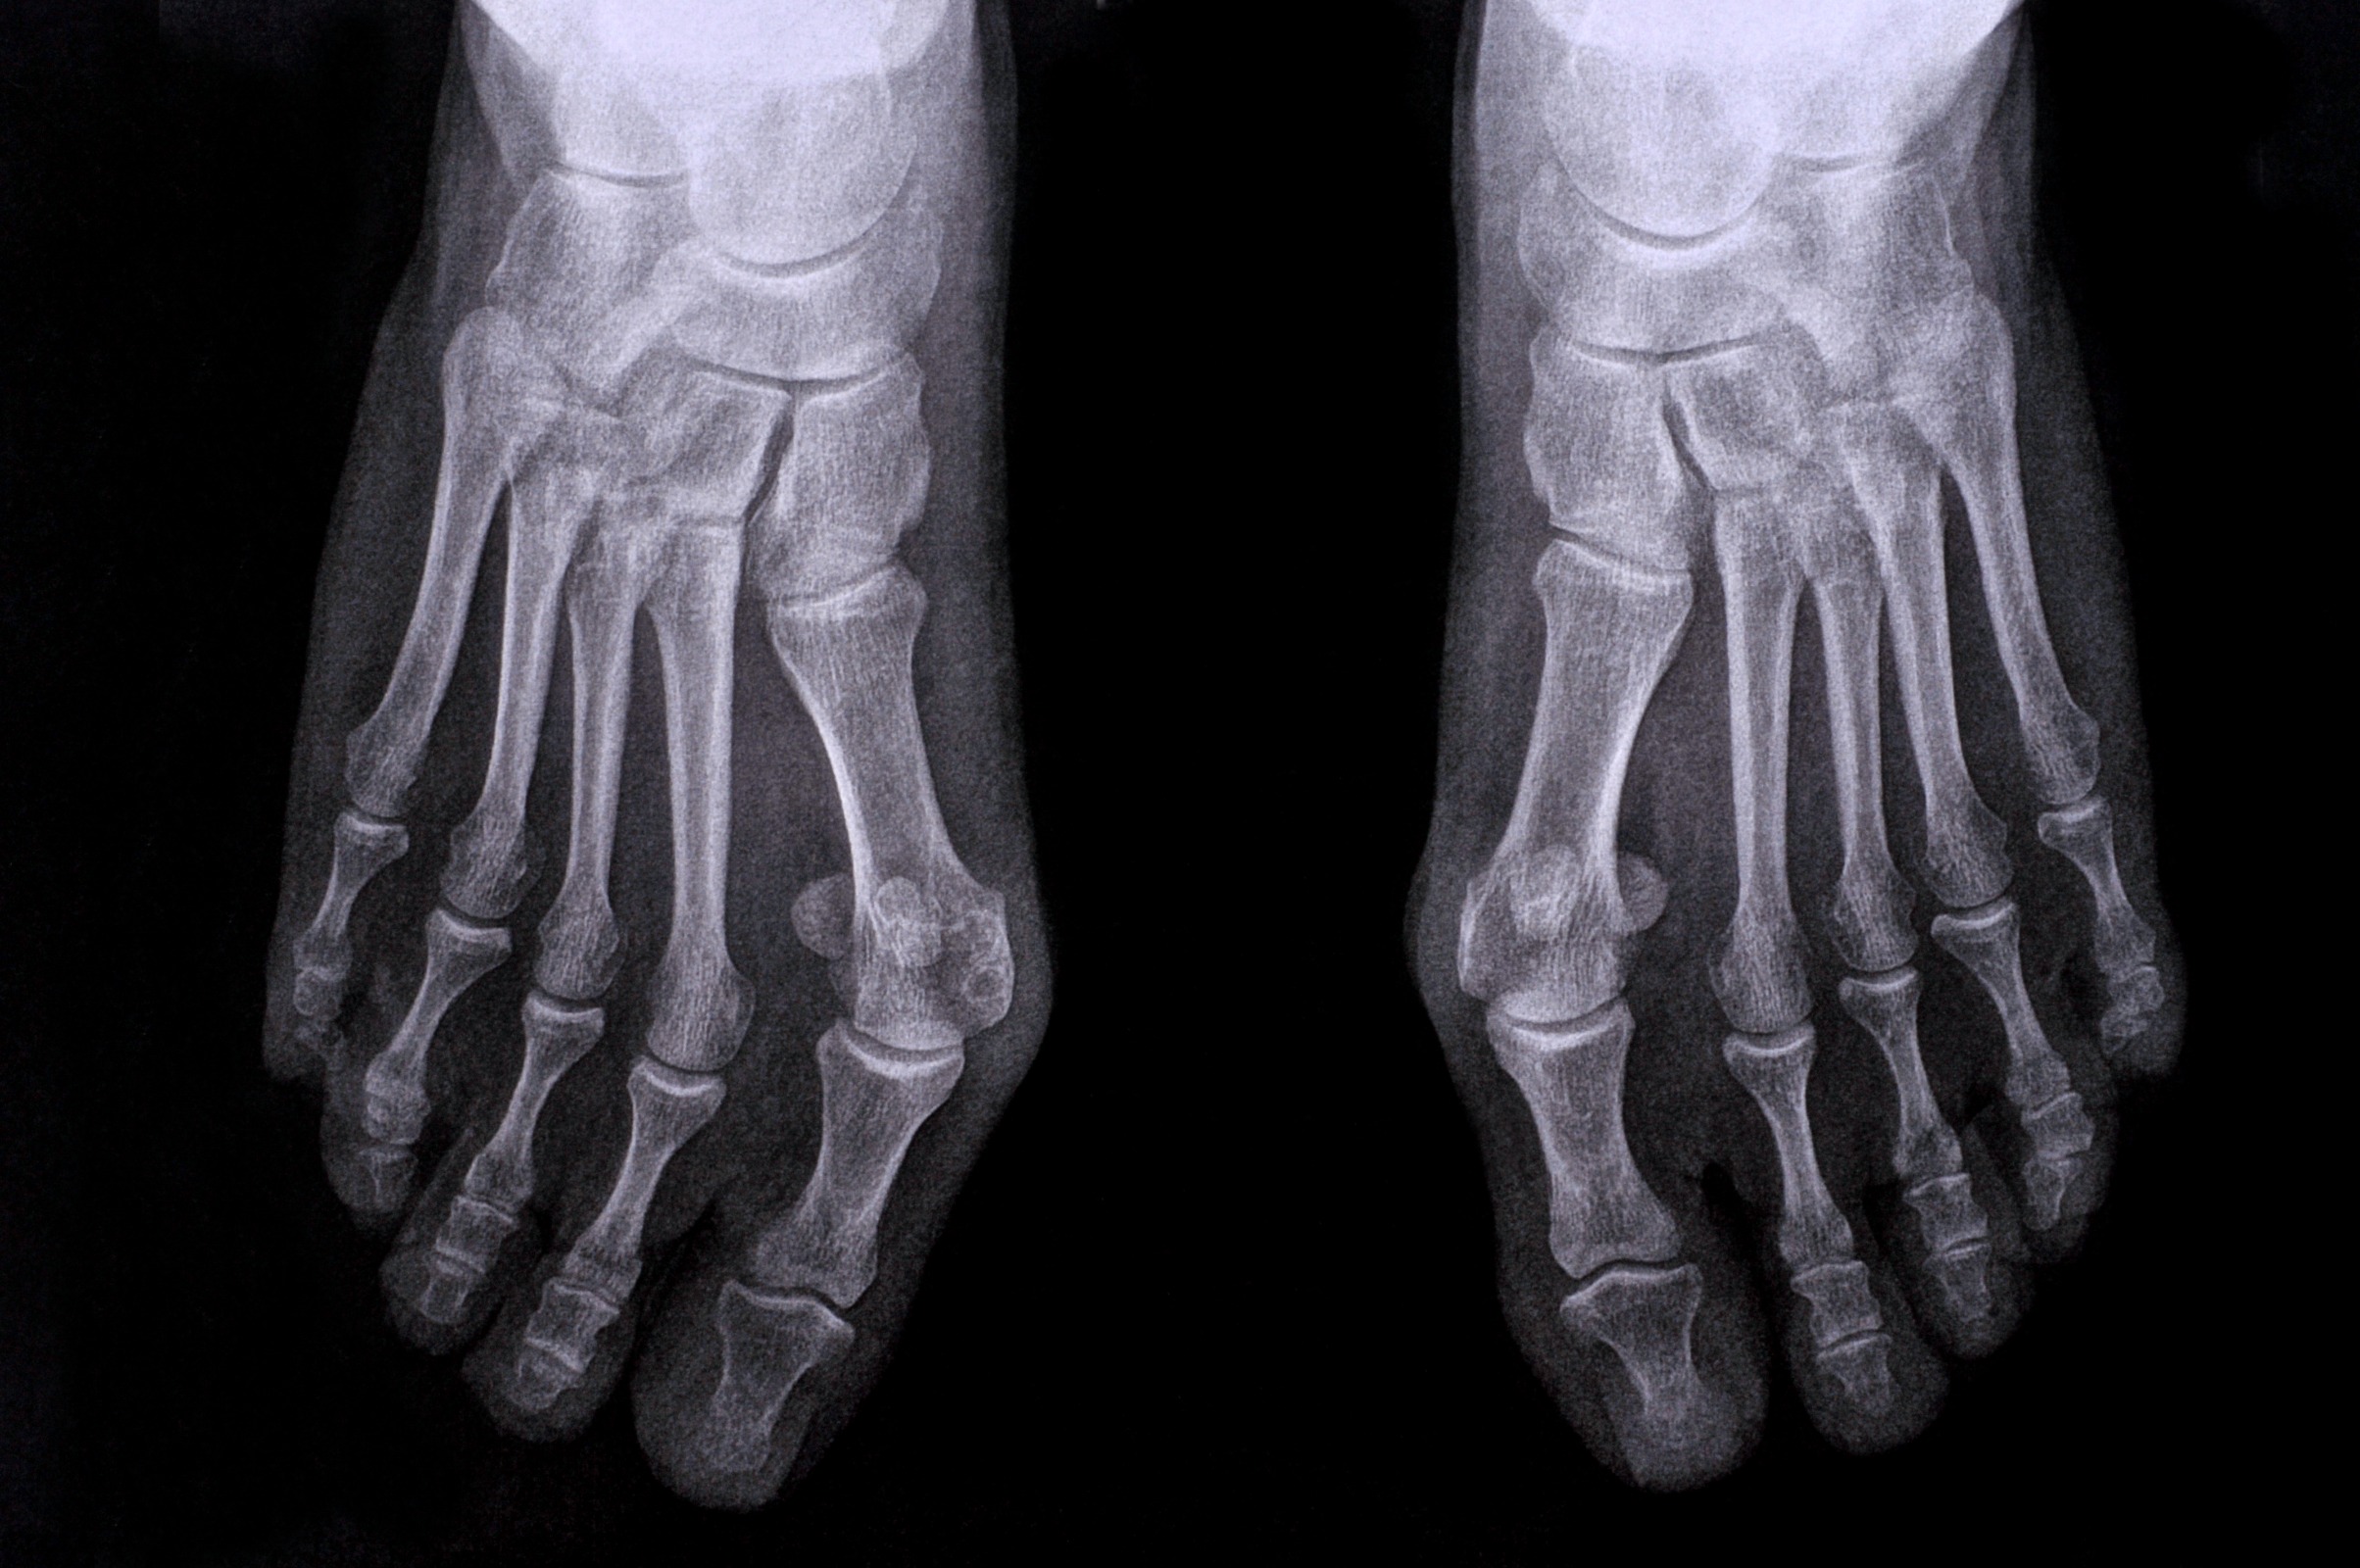

Hast du dich schon einmal gefragt, was diese knöcherne Erhebung an der Seite deines Fusses ist? Möglicherweise handelt es sich um einen Ballenzeh, auch als Hallux valgus bekannt. Obwohl ein Hallux valgus in den meisten Fällen relativ harmlos ist und oft keinen medizinischen Eingriff erfordert, kann er unbehandelt jedoch eine Menge Schmerzen und Beschwerden verursachen und deine Lebensqualität drastisch einschränken.